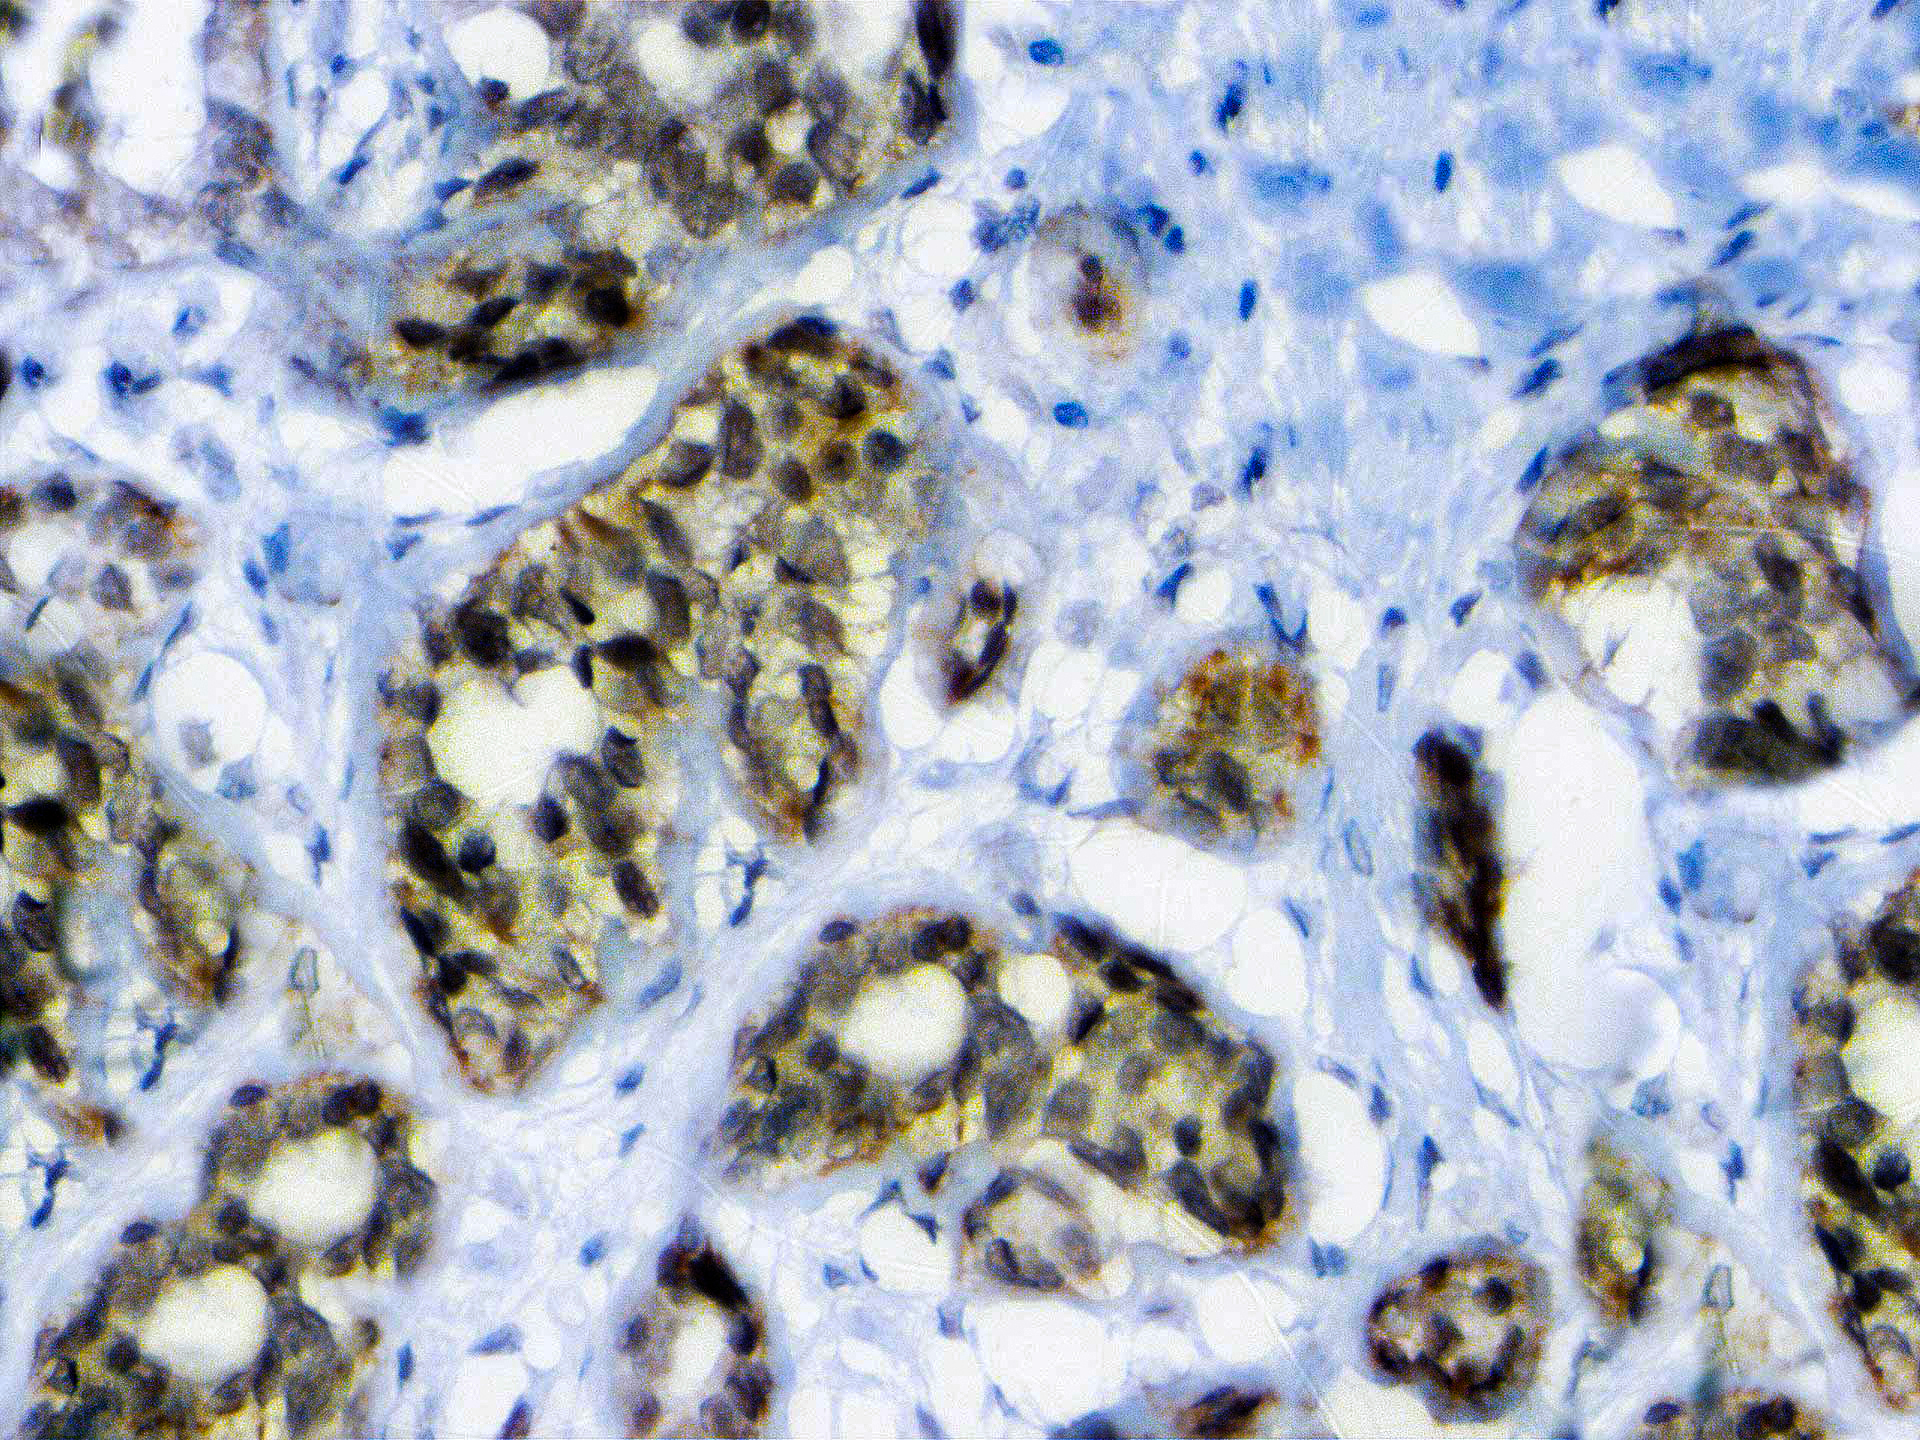

BAP1 (BRCA1-Associated Protein 1) was initially identified as a protein that binds to BRCA1. BAP1 is a tumor suppressor that is believed to mediate its effects through chromatin modulation, transcriptional regulation, and possibly via the ubiquitin-proteasome system and the DNA damage response pathway. Germline mutations of BAP1 confer increased susceptibility for the development of several tumors, including uveal melanoma, epithelioid atypical Spitz tumors, cutaneous melanoma, and mesothelioma. Somatic BAP1 mutations are seen in cutaneous melanocytic tumors (epithelioid atypical Spitz tumors and melanoma), uveal melanoma, mesothelioma, clear cell renal cell carcinoma, and other tumors. BAP1 immunohistochemistry is particularly useful in differentiating malignant mesothelioma (nuclear negative) vs. reactive mesothelial proliferation (nuclear positive).

| Positive Control Tissue | Breast carcinoma |

| Cellular Localization | Nuclear and Cytoplasmic |